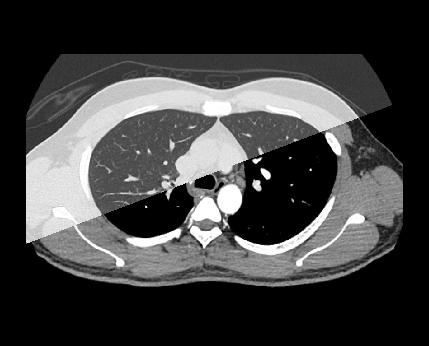

Scan has two phases, which are pre-contrast and arterial. It is hard to define an accurate time for the chest arterial phase, which is nearly 25 seconds from contrast injection, because it changes according to the patient’s ejection fraction. So, triggering method can be used to initiate a timelyarterial phase by assessing patient’s real-time arterial enhancement. Please reach our thoracic aortogram article for more information about bolus tracking.

- Plan both scan slabs to cover from lung apex to posterior costophrenic sulci.

- Acquire both phases under suspended full inspiration.